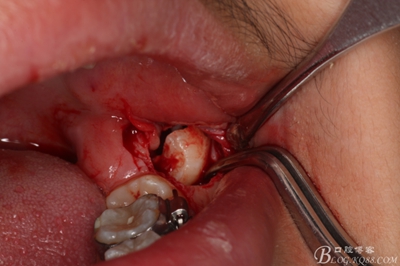

圖6.兩個(gè)切口的交界處翻瓣

6_副本.jpg

圖7.翻開(kāi)粘骨膜瓣。

7_副本.jpg

圖8。暴露出頰側(cè)骨壁,38完全位于骨內(nèi)

8_副本.jpg

圖9.高速拔牙手機(jī)去骨

9_副本.jpg

圖10.去骨后暴露出38的牙冠

10_副本.jpg